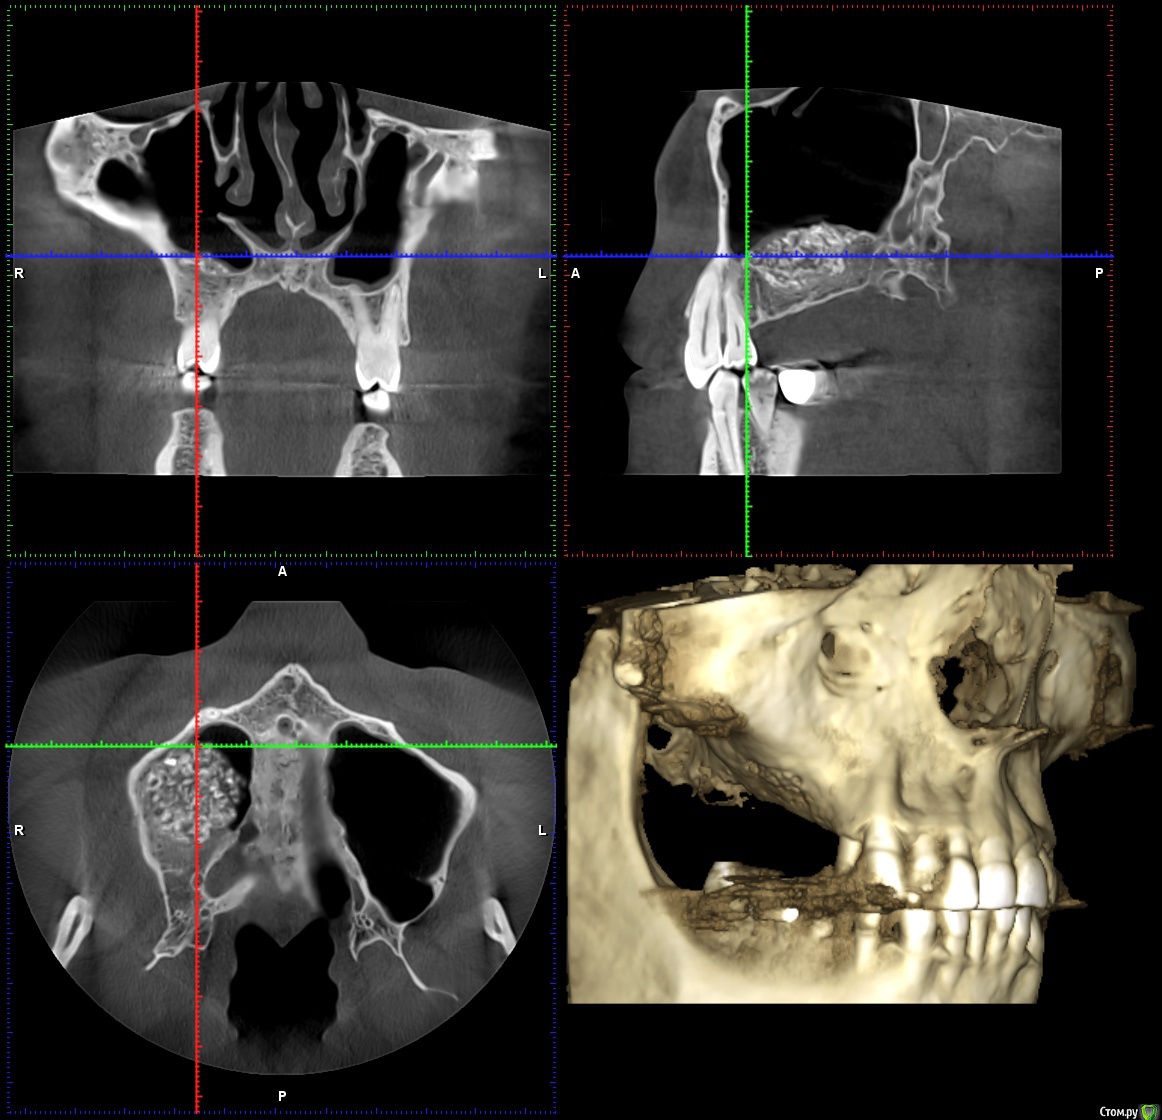

Reyb Опубликовано 14 марта, 2018 Поделиться Опубликовано 14 марта, 2018 Здравствуйте уважаемые доктора.У меня такая проблема,в декабре 2016 года мне делали открытый синус лифтинг справа.Через день-два после операции у меня начались боли,что я воспринял как норму.Дней через 9 врач снял швы,осмотрел и сказал,что всё в норме и боли должны скоро пройти.Через месяц,когда стало можно сморкаться,сразу заметил что справа высмаркивается слизь с кровью,да и к тому же боль не проходила.Пошёл к своему врачу.Он осмотрел и сказал,что всё в приделах нормы (по панорамному снимку).Спустя 1,5 месяца,при сморкании стал замечать ещё и гной с кровью.Спустя ещё где-то 2-3 недели периодически стало закладывать нос.Когда подошло время ставить импланты врач посмотрев КТ сказал,что нельзя,так-как гайморит справа и направил к лору.Пролечившись у лора,стал сомневаться в продолжении имплантации.Спустя 15 месяцев ноющая боль на стороне операции осталась и при сморкании иногда что-нибудь да вылетит из правой ноздри (сгустки крови или почти сухая корка в слизи).На сегодняшний день как и с первых дней после синус лифтинга самочувствие как-будто приболел,писк в ушах(появлялся всегда когда чем-нибудь болею).На КТ просматривается неоднородность и затемнения в материале.Что это,отторжение,инфицирование или норма?К своему стоматологу претензий не имею так-как сделано было на мой взгляд на высоком уровне.Что посоветуете делать в моём случае? КЛКТ от 1.03.2018г.http://my-files.ru/qki4xs Ссылка на комментарий

wladdX Опубликовано 15 марта, 2018 Поделиться Опубликовано 15 марта, 2018 Несколько скринов Ссылка на комментарий

Irouil Опубликовано 15 марта, 2018 Поделиться Опубликовано 15 марта, 2018 Когда КТ делали? У Вас открыт нижний носовой ход в пазуху, уже это одно может вызывать выделения из ноздри, на которые Вы жалуетесь. Да и болевые ощущения, в принципе. Кажется графт не звонил, слизистая спокойная вокруг него, но может быть и не пророс новой костью. Надо готовиться под имплантацию, я считаю, если при сверлении обнаруживается несостоятельность графта - удаление его из пазухи и реоперация через месяц Ссылка на комментарий

Reyb Опубликовано 15 марта, 2018 Автор Поделиться Опубликовано 15 марта, 2018 Когда КТ делали? У Вас открыт нижний носовой ход в пазуху, уже это одно может вызывать выделения из ноздри, на которые Вы жалуетесь. Да и болевые ощущения, в принципе. Кажется графт не звонил, слизистая спокойная вокруг него, но может быть и не пророс новой костью. Надо готовиться под имплантацию, я считаю, если при сверлении обнаруживается несостоятельность графта - удаление его из пазухи и реоперация через месяц Когда КТ делали? У Вас открыт нижний носовой ход в пазуху, уже это одно может вызывать выделения из ноздри, на которые Вы жалуетесь. Да и болевые ощущения, в принципе. Кажется графт не звонил, слизистая спокойная вокруг него, но может быть и не пророс новой костью. Надо готовиться под имплантацию, я считаю, если при сверлении обнаруживается несостоятельность графта - удаление его из пазухи и реоперация через месяцКТ делал 1 марта 2018г. До синуслифтинга выделений не было.Такого чтоб самопроизвольно из носа текло,нет.Только при сморкании бывает,что вылетит не большой сгусток крови. Ссылка на комментарий